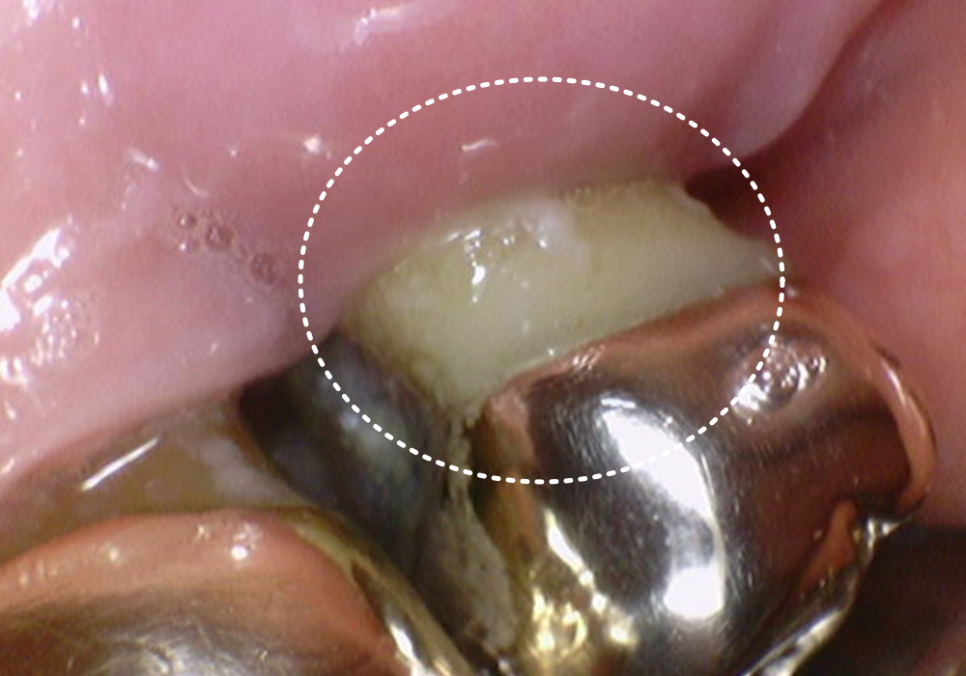

얼마 전 오른쪽 위 어금니가

심하게 흔들린다며 한 환자분이 내원하셨어요.

입안을 살펴보니 예전 금니 아래로

잇몸이 쑥 내려가 뿌리가 훤히 드러나 있었고,

잇몸은 이미 붉게 부어있는 상태였죠.

잇몸이 내려가다 보니 치아 사이 빈 공간으로

음식물이 가득 끼어있었는데,,

치아 사이는 칫솔이 잘 닿지 않아

남은 음식물이 잇몸을 더 빠르게 녹이고 있었습니다.